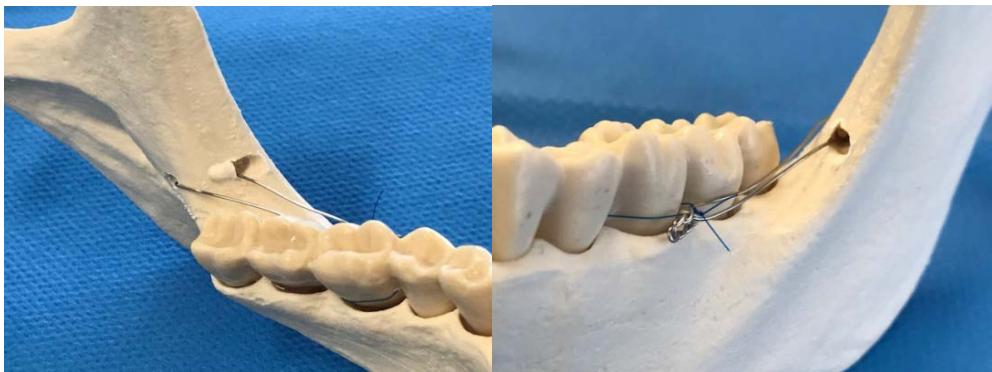

Une perforation de la branche montante est réalisée, sous irrigation, grâce à une fraise boule montée sur piece à main chirurgicale, afin de faire passer le fil d'osteosynthèse de part et d'autre, en protégeant le nerf lingual.

Un fil d'ostéosynthèse (de $4/10^{\text{ème}}$ de mm de diamètre) est ensuite inséré dans la perforation. Les deux brins seront toronnés et repliés au niveau de l'appareil d'orthodontie pendant le geste chirurgical afin de ne pas génér le patient. La mise en traction par l'orthodontiste peut avoir lieu rapidement après la mise en place du système.